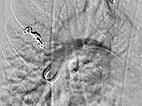

Bei der Abklärung der Grunderkrankung wurde in der Kontrastmittel-Sonographie ein pulmonaler Rechts-links-Shunt gefunden, die Computertomographie bestätigte den Befund mehrerer pulmonaler AVM. Aufgrund der Größe, Indikation zur Embolisation. Die digitale Subtraktionsangiographie zeigt eine bereits superselektiv kanülierte pulmonale AVM im Oberlappen mit der typischen aneurysmatisch erweiterten arteriovenösen Kommunikation.